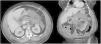

La pancreatitis aguda es una patología común y potencialmente grave que tiene un curso clínico muy variable. Este artículo pretende revisar el papel de las distintas técnicas de imagen en el manejo de esta entidad, describir sus principales manifestaciones radiológicas y la nomenclatura específica asociada a esta entidad.

Acute pancreatitis is common; the clinical course of this potentially severe condition varies widely. This paper aims to review the role of different imaging techniques in the management of acute pancreatitis, describe the main imaging findings for this entity, and explain the terms and criteria used to classify them.